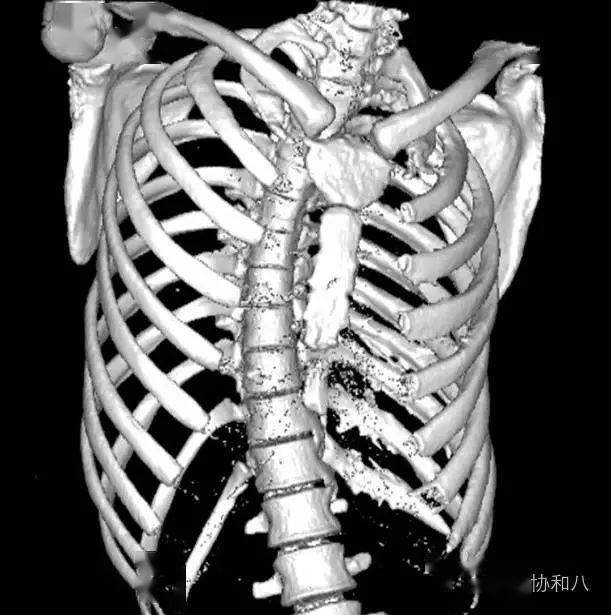

二一五医院骨科医院脊柱外科成功治疗一名胸椎结核患者

图片尺寸651x800